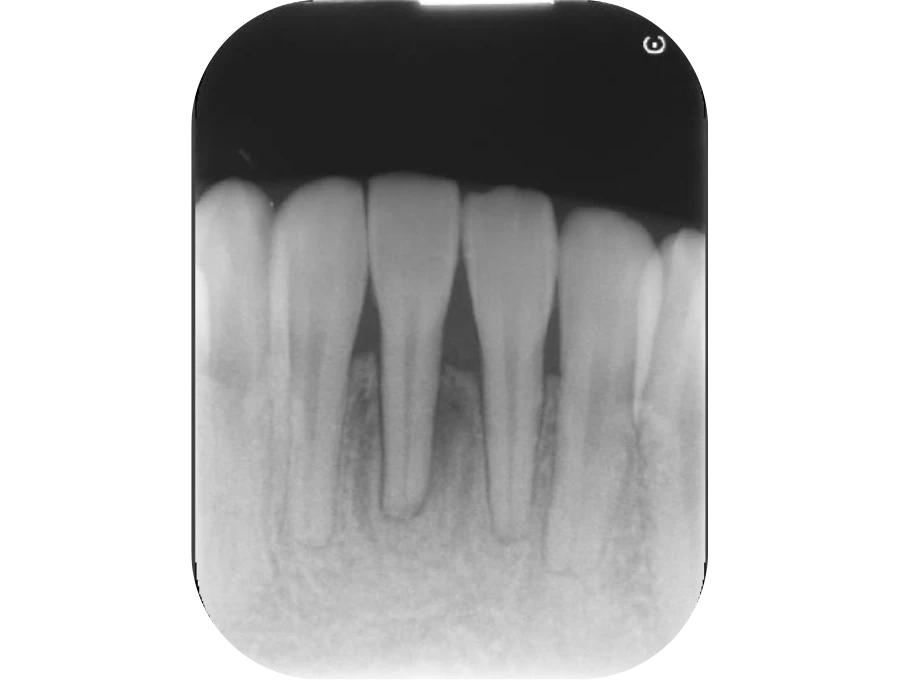

正確な診断

歯周ポケット測定やレントゲン・CT解析など、多角的な検査で歯周病の進行度と原因を正確に把握します。患者さま一人ひとりに最適な治療計画を立て、根拠ある治療につなげます。

精密検査

実際にお口の中の状態をチェックしていきます。レントゲン撮影にて歯や骨の検査を行い、虫歯や治療痕のチェック、歯周病検査などの各種検査を行い、総合的な診断を下します。